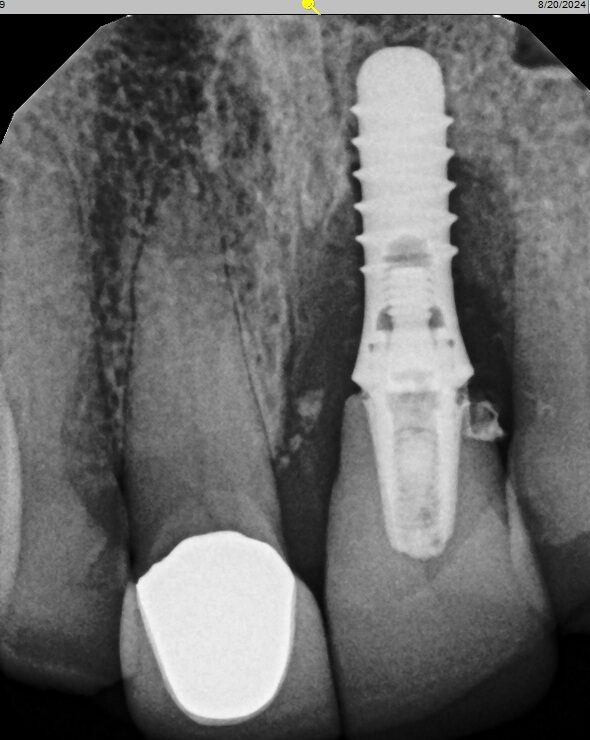

Before

After